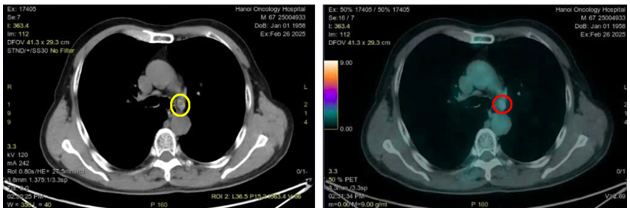

Hình 4: Hình ảnh tổn thương u phổi thùy dưới phổi trái kích thước 10x15mm trên CT (vòng tròn màu vàng) và PET/CT (vòng tròn màu đỏ) tăng chuyển hóa FDG (SUVmax: 9,8)

Hình 5: Hình ảnh hạch trung thất ở cửa sổ chủ phổi đường kính 7mm trên CT (vòng tròn màu vàng) và PET/CT (vòng tròn màu đỏ) tăng chuyển hóa FDG (SUVmax: 2,69)